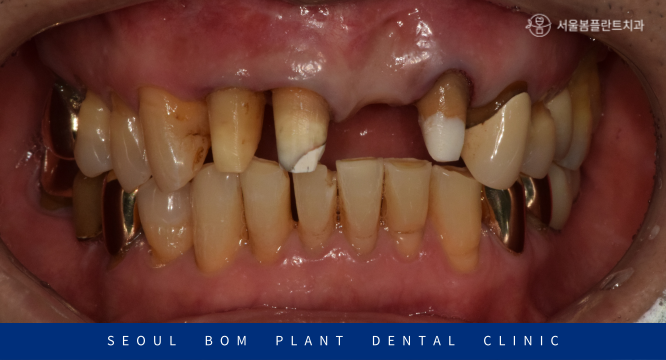

먼저 구강 내를  확인해 보았더니

위턱의 앞니가 오른쪽 두 번째 앞니(#12)부터

왼쪽 두 번째 앞니(#22)까지 총 4개의 보철물로 이루어진 브릿지 상태로

구강 위생 관리 부족으로 인해 잇몸 퇴축이 심하였으며,

외상으로 인한 충격으로 양측 첫 번째 앞니(#11,21) 사이가

파절되어 뒤틀려 있는 것으로 보였는데요.

이 경우 파절된 부위를 다시 접합을 시킨다거나

수정을 하는 것은 불가능하기 때문에

기존 보철물을 제거한 뒤 재보철치료가 필요하였습니다.